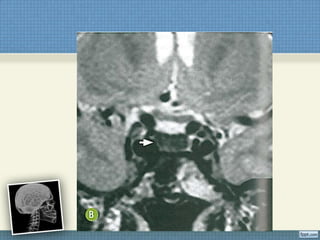

ACHADOS DE IMAGEM

RM de Crânio + Cervical + Torácica

• T1:

 Discreto espessamento da medula espinal sem

evidência de alteração de sinal ou impregnação

pelo contraste;

• T2:

– Hiperssinal linear contínuo e simétrico dos

funículos posteriores e laterais. Não é

necessário o achado combinado.